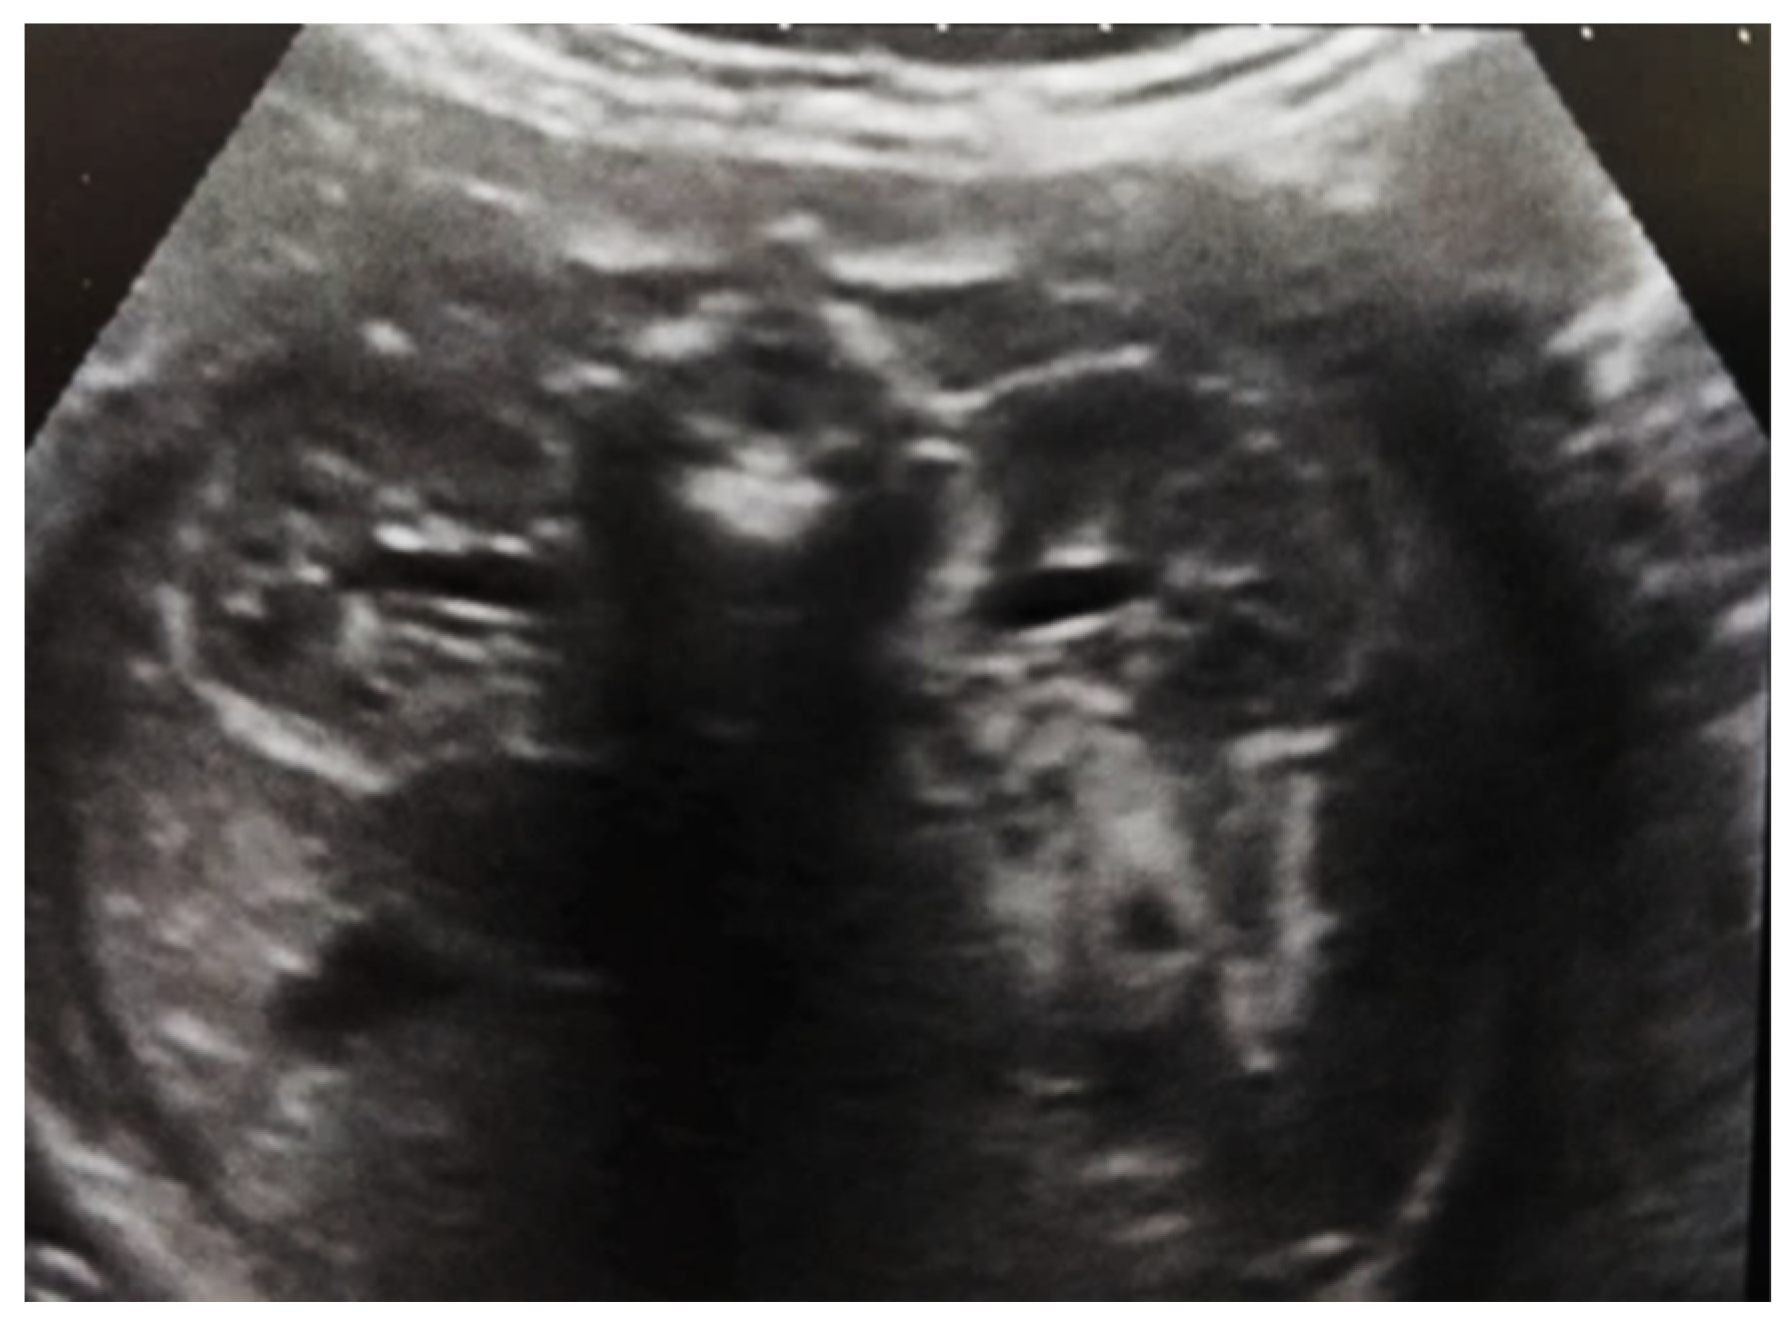

Our experience with congenital malformations of the urinary system refers to the following clinical case (Figure 2, Figure 3, Figure 4, Figure 5, Figure 6, Figure 7, Figure 8 and Figure 9). In the first case, during pregnancy, the 21-week ultrasound determined bilateral renal pyelectasia. The fetus had hydronephrosis on the right; at 31 weeks, it had bilateral hydrocalconephrosis; and at 32 weeks, bilateral pyelectasia. It suffered premature birth at 36 weeks, with complicated anomalies of the forces of contraction, prolonged birth, and birth weight of 2200 g. Postnatal ultrasonography was supplemented by intravenous urography, and bilateral hydronephrosis was determined. Hydrocalconephrosis on the left was discovered. The complete diagnosis was established: congenital renal malformation; bilateral pyelectasia; bilateral hydronephrosis; hydrocalconephrosis on the left; and severe reduced glomerular filtration rate (GFR), GFR > 2SD below mean.

Figure 4. Ultrasound at 31st week of gestation. Bilateral hydrocalconephrosis.